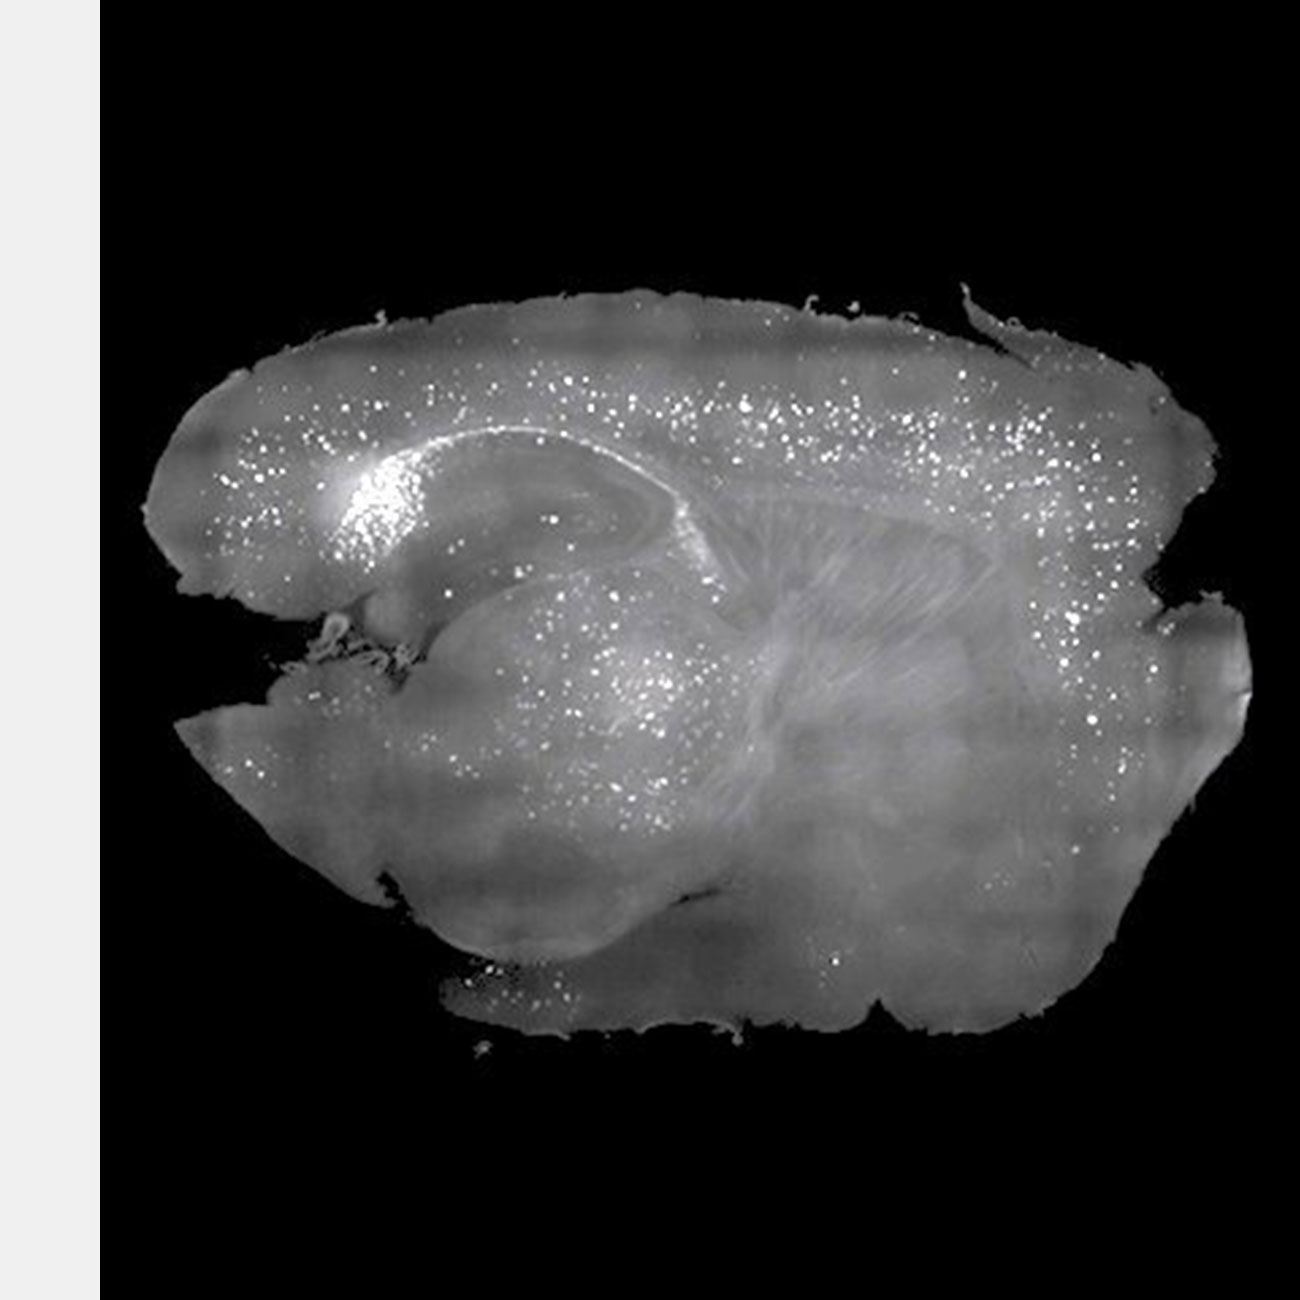

Амилоидные бляшки, которые мешают работе мозга мышей, удалили с помощью звуков. В будущем эти опыты могут привести к появлению дешевого и безлекарственного способа лечения нескольких форм деменции.